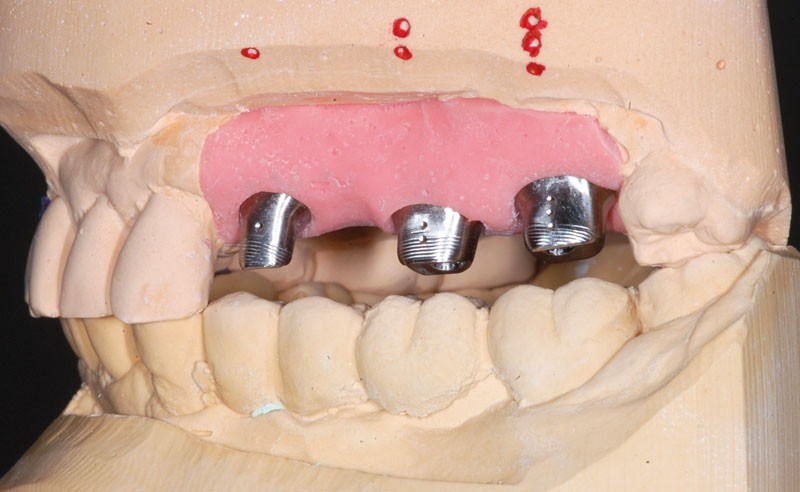

Une fois les transferts pick-up EV® transvissés, le porte-empreinte Tray, fenestré en regard des transferts, est chargé de matériau monophase Impregum™ Penta™ Soft (3M ESPE). Du matériau est déposé autour des transferts à l’aide d’une seringue. Après dévissage des transferts, ces derniers sont emportés dans l’empreinte et les analogues d’implants sont transvissés.

Le modèle de travail est fabriqué au laboratoire, des piliers CFAO Atlantis™ sont réalisés en fonction du bridge antagoniste transitoire.